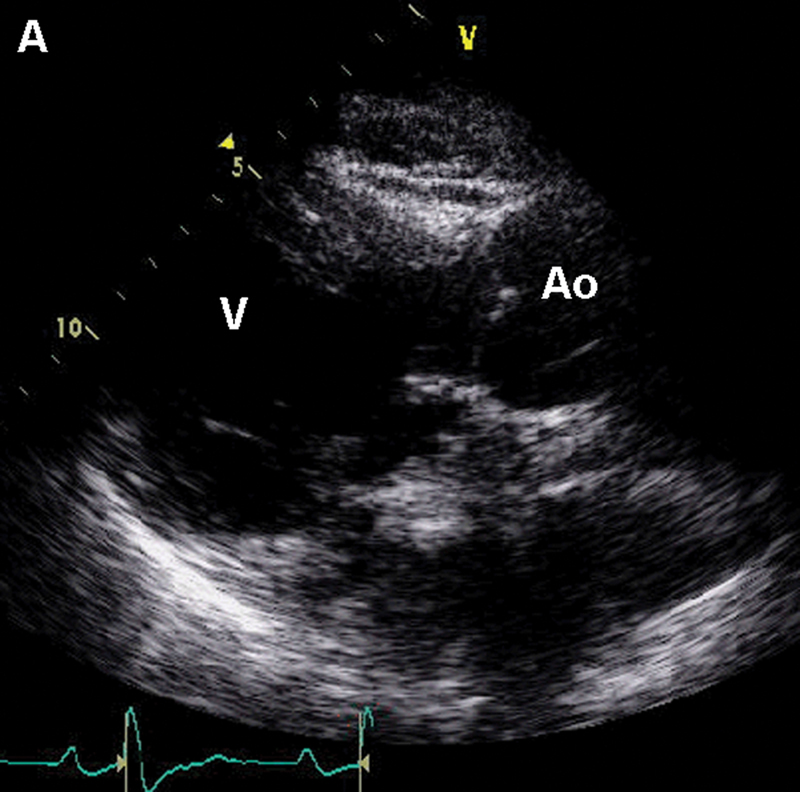

فحوصات تشخيصية لبعض امراض القلب والشرايين التاجية